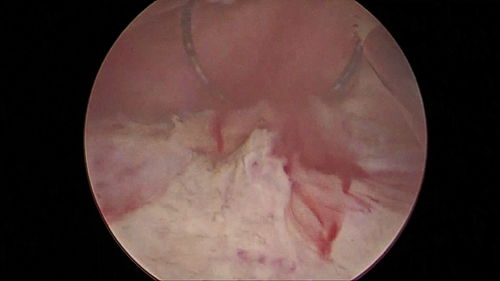

影像学检查:如经直肠或腹部超声、CT或磁共振成像(MRI),可以精确测量前列腺的三维尺寸并计算其体积。

直肠指检(DRE):医生通过手指触诊,可以直观感受前列腺的大小、质地、表面光滑度及有无结节,初步判断其健康状况。